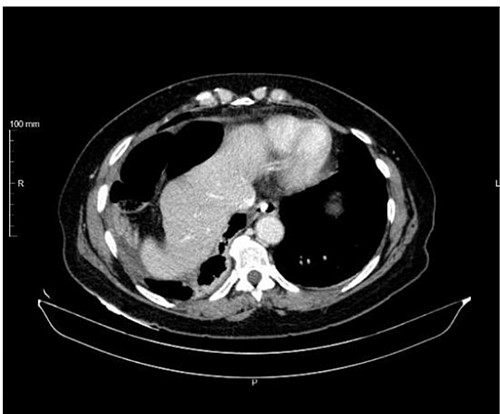

An abdominal computed tomography (CT) scan was performed, which identified an internal hernia at the root of the right mesentery, an apparent abscess in the right lung base (65 × 55 mm) (Fig. 1) as well as elevation of the right diaphragmatic hemi-dome with Chilaiditi sign (Fig. 2).